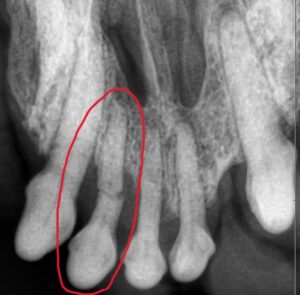

全身麻酔をかけてから、すべての歯のレントゲン撮影と診断を行います。

レントゲンでは歯が折れている様子がはっきりと分かります。

神経が通っている部分で折れているため、放置してしまうと感染のリスクがあります。

そのため、折れている歯は抜歯を行いました。